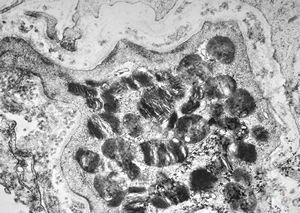

M, 62y. | mitosis … angiomatous tumor, v.s. Kaposi sarcoma

M, 62y. | angiomatous tumor, v.s. Kaposi sarcoma

M, 62y. | Weibel-Palade body - angiomatous tumor, v.s. Kaposi sarcoma